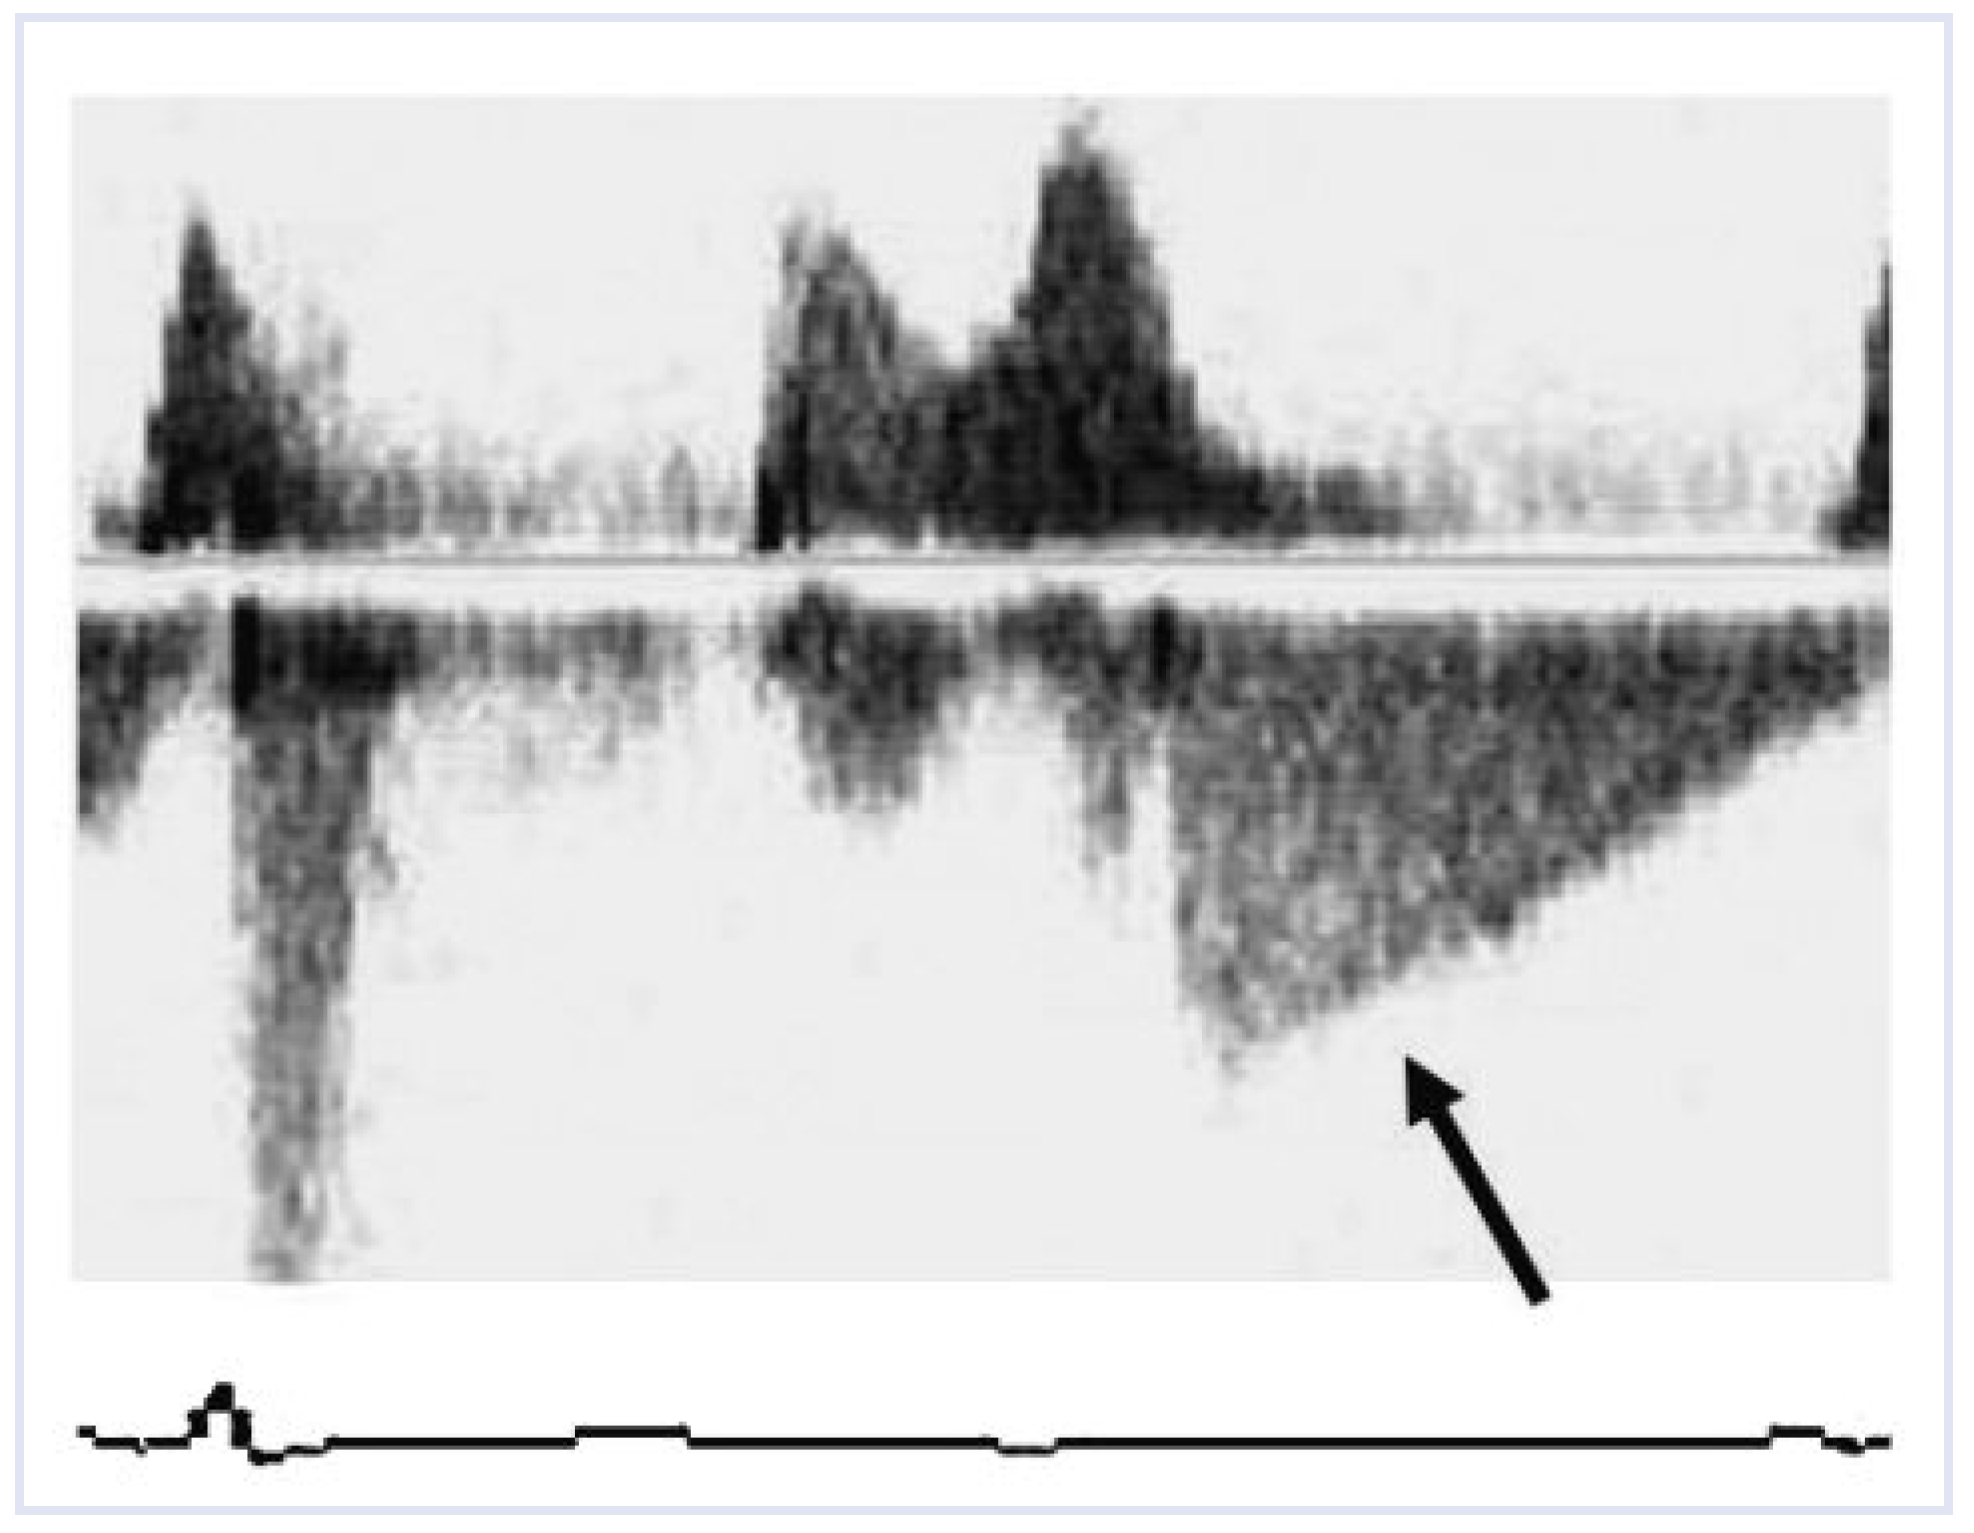

Figure 2. Continuous wave Doppler on admission showing mitral flow with only minimal early systolic and moderate to severe diastolic mitral regurgitation (arrow).

A 90-year-old female patient was admitted with congestive heart failure. The ECG showed a heart rate of 40 beats per minute with Mobitz II second-degree atrioventricular (AV) 2:1 block (Figure 1). Two-dimensional echocardiography revealed concentric left ventricular (LV) hypertrophy with normal systolic function (LV ejection fraction 70%) and dilatation of the left atrium. Doppler echocardiography detected only minimal early systolic and moderate to severe diastolic mitral regurgitation (Figure 2), mild-to-moderate, particularly diastolic tricuspid regurgitation, and elevated pulmonary artery pressure. Subsequently a VDD pacemaker was implanted and transthoracic echocardiography was repeated with a normal AV conduction time. Doppler echocardiography showed only minimal early systolic mitral regurgitation without diastolic regurgitation (Figure 3) and only minimal tricuspid regurgita-tion. Although clinical signs of congestive heart failure had already improved after initiation of medical therapy, they disappeared only after implantation of the pacemaker.